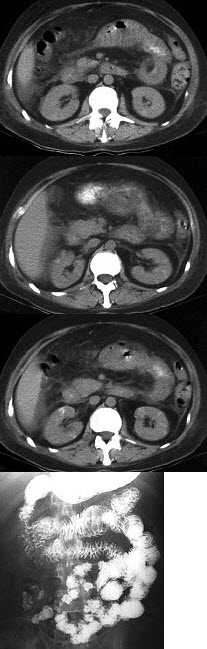

男,32岁,阵发性腹痛、腹胀,伴恶心、呕吐,腹部可触及包块,影像检查如图,最佳的诊断是什么( )

A:小肠肿瘤

B:麻痹性肠梗阻

C:空肠套叠

D:回肠套叠

E:结肠套叠